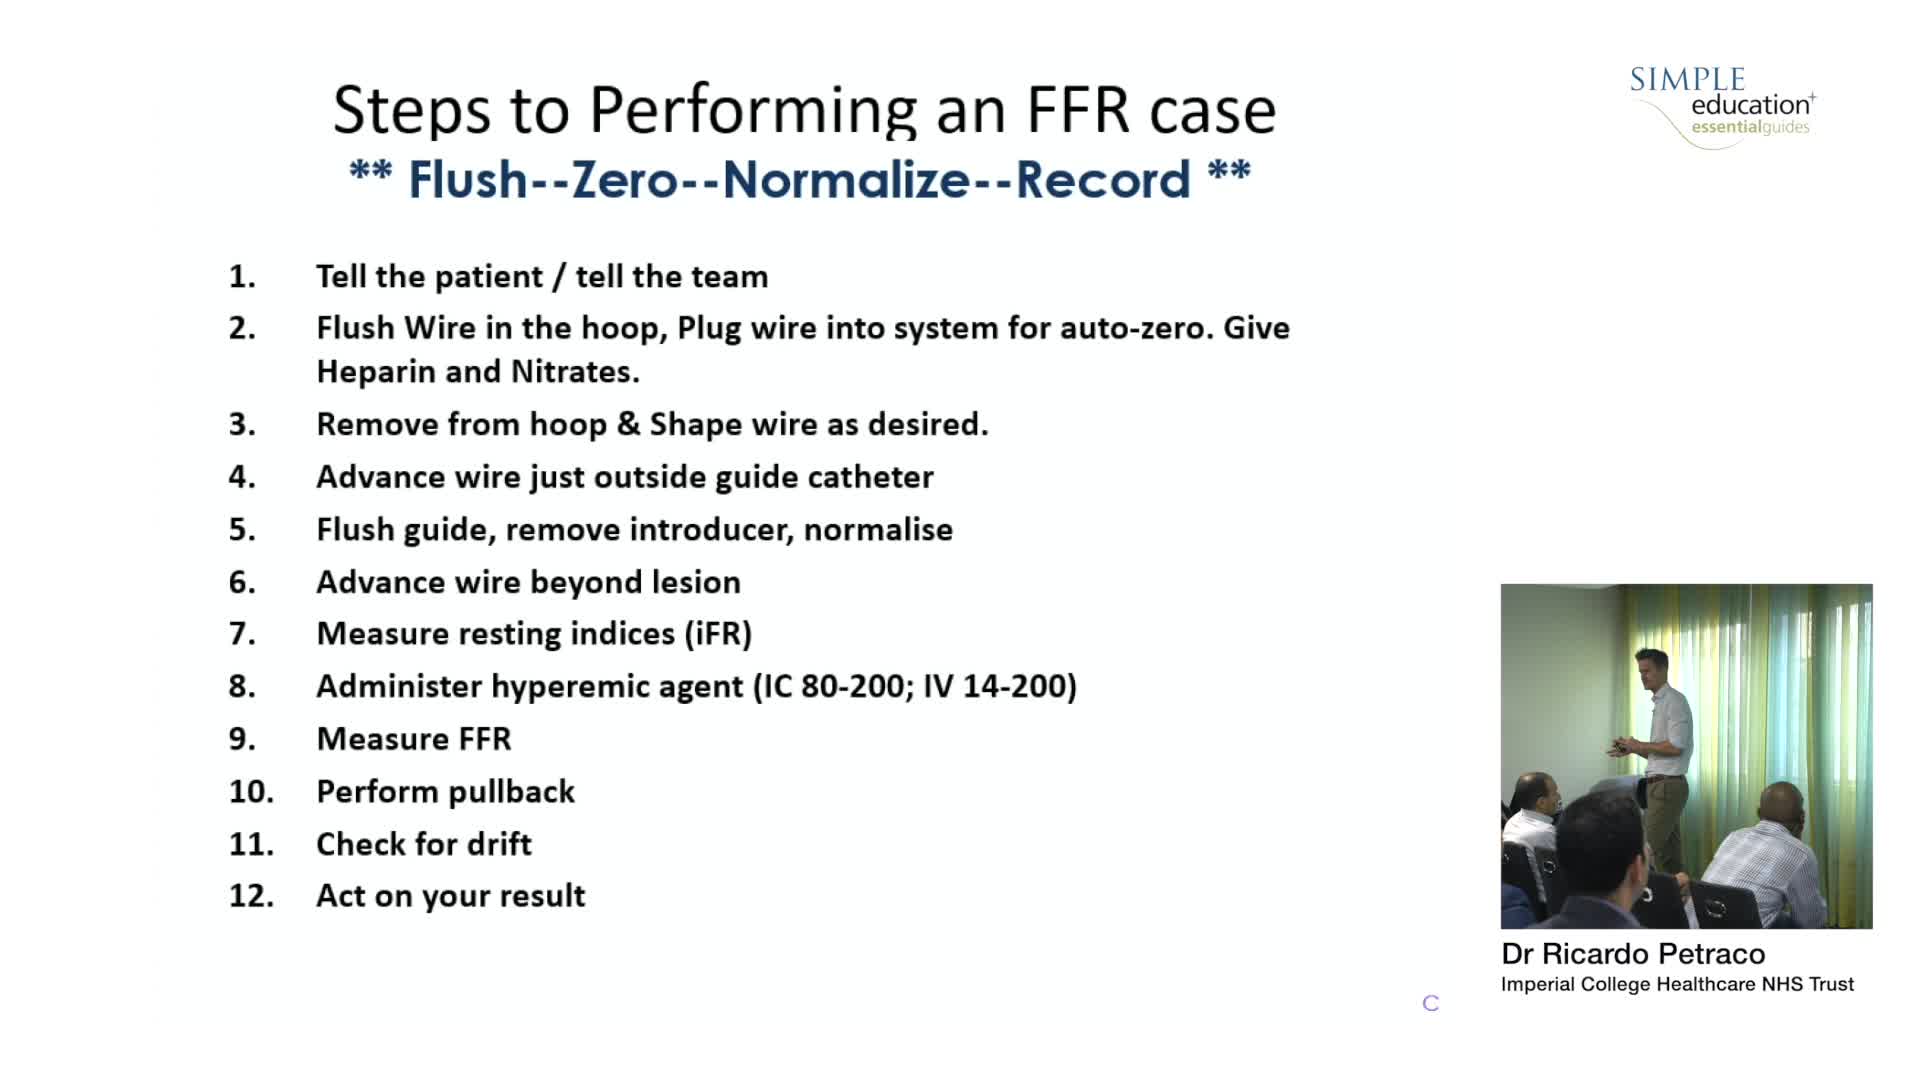

Breakout session: Common pitfalls of FFR and iFR assessment - Dr Ricardo Petraco

How to perform iFR and FFR, and best-practice measurement tips and tricks - Dr Ricardo Petraco